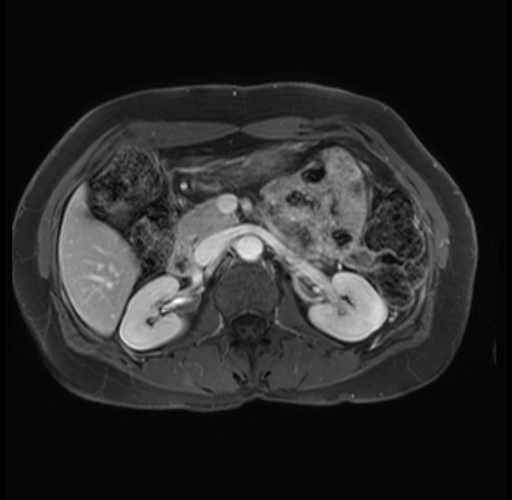

Imaging Analysis

Look through the patient's CT scan to identify any areas of concern for the necessary procedure.

Based on your CT findings, which issue(s) are present and would give reason for "planned slowing down moment(s)" in this case?